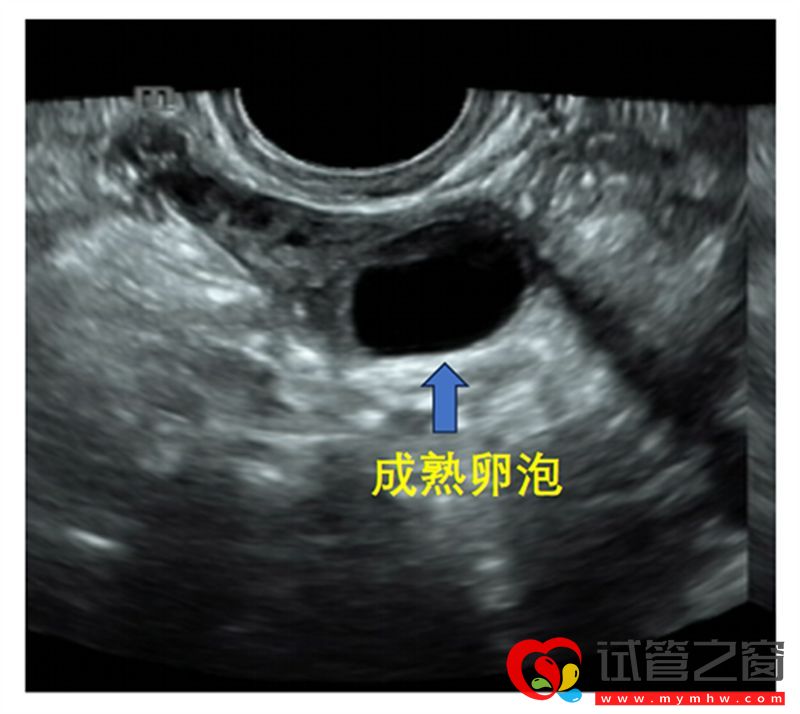

B超监测成熟卵泡

成熟卵泡(月经周期14天左右):卵泡直径达到18-25mm时,外形饱满呈圆形或椭圆形,内壁薄而清晰,位置移向卵巢表面并向外突出,如果卵泡一侧内壁上探及卵丘(出现率约20%),表现为细小点状高回声 ,意味着排卵过程将在24小时内开始。